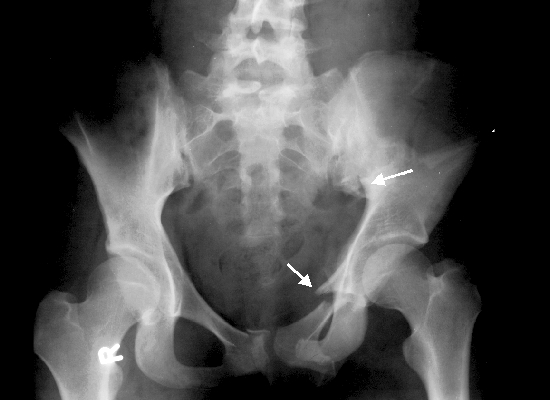

Перед началом лечения в медицинском учреждении проводится тщательная диагностика травмы. Первым этапом является ручной осмотр. Во время пальпации специалисты определяют точное месторасположение перелома, тип повреждения (одностороннее или двухстороннее) и могут обнаружить осколки костей.

Для получения более детальной информации о травме и степени повреждения используется рентген. Это исследование позволяет увидеть место перелома и наличие смещения. Разрывы связок и мышечной ткани, а также повреждения внутренних органов выявляются с помощью УЗИ и МРТ.